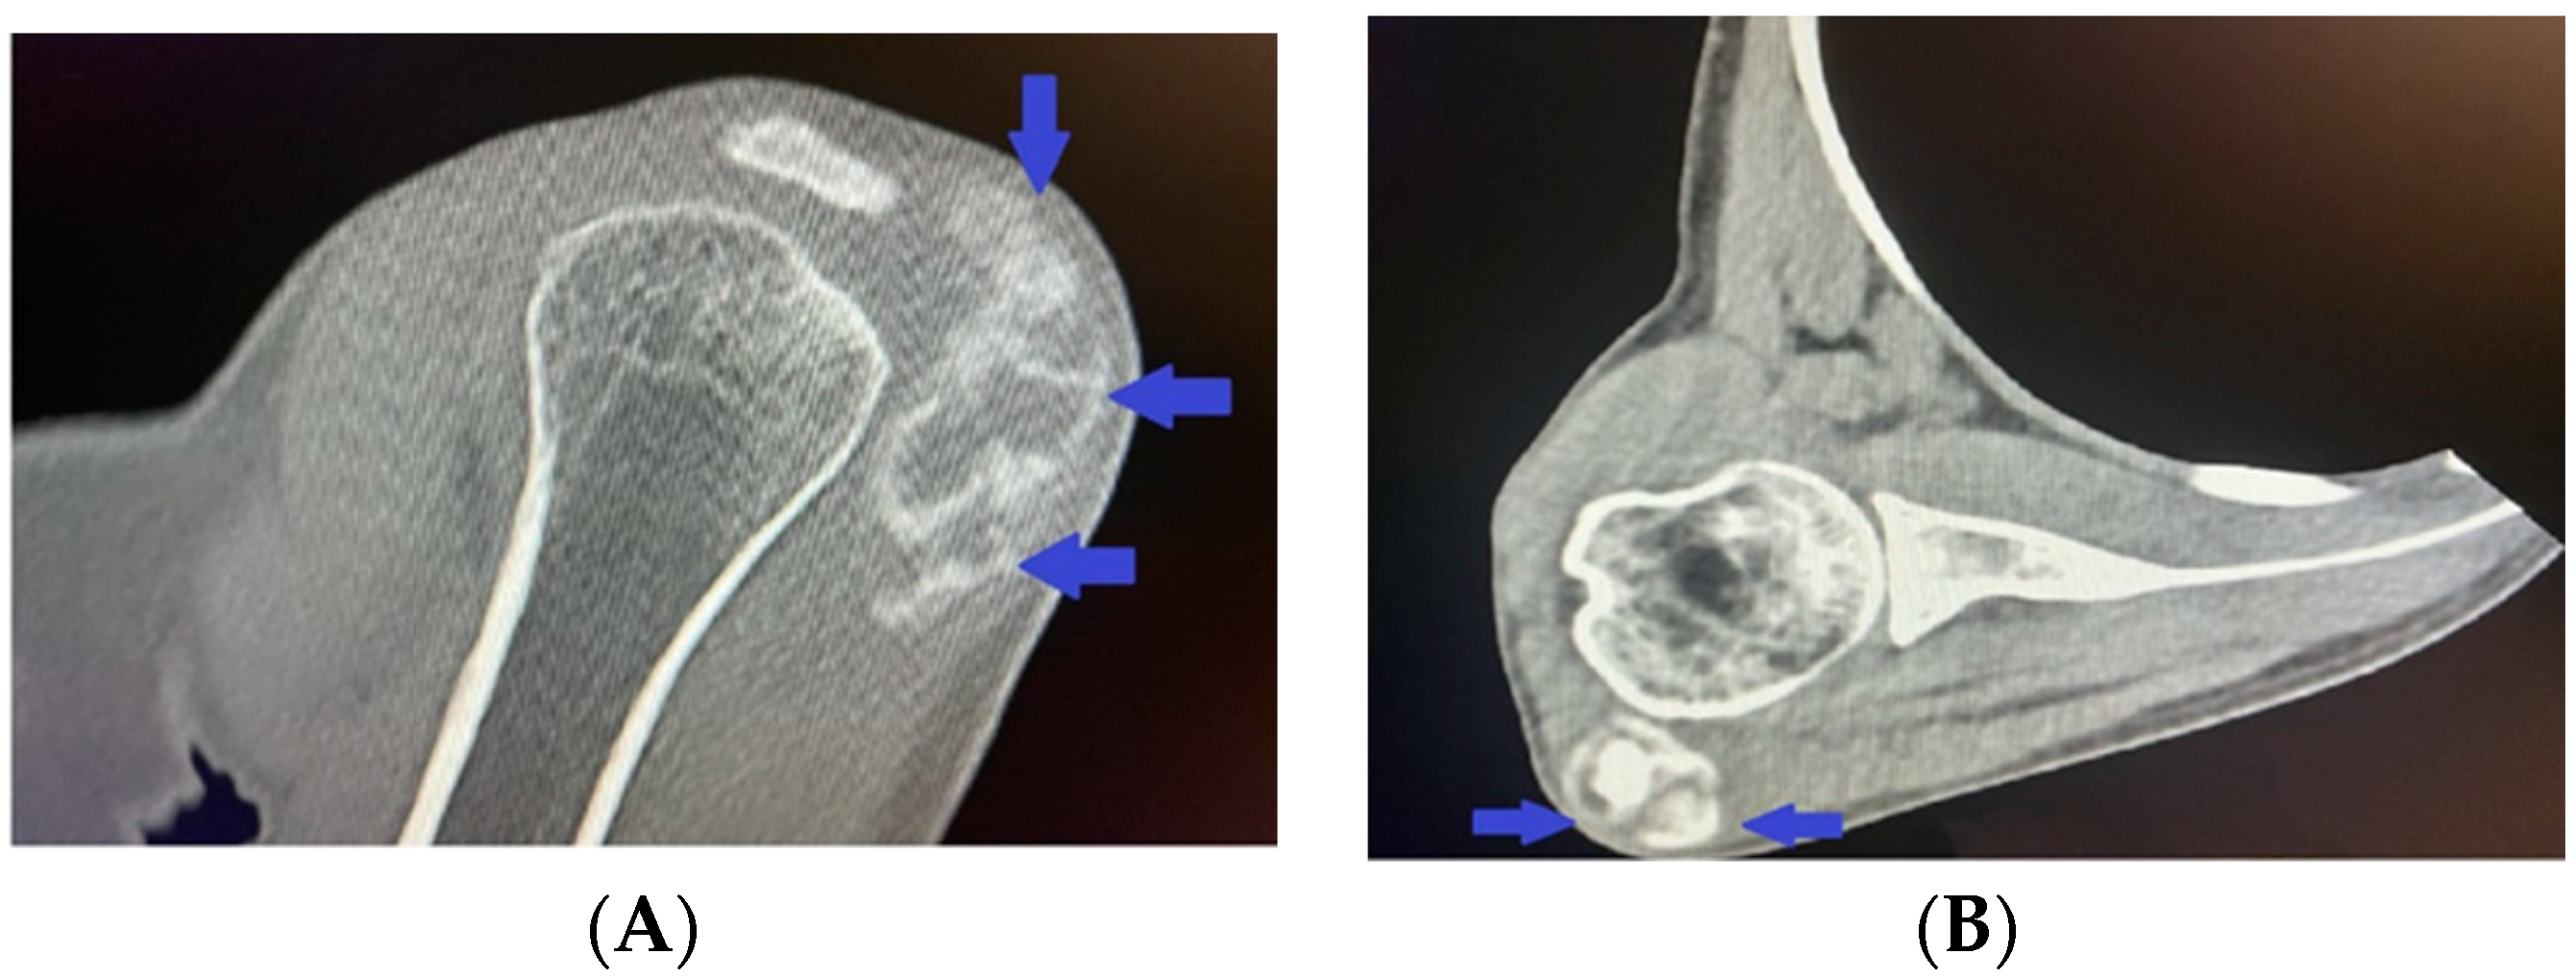

The patient saw her general practitioner in October 2021 due to swelling in the neck region and a pulsing lump on the left side of the neck. Following a clinical assessment, the physician recommended an ultrasound, which showed dilatations of 10 mm in the right external carotid artery and 12 mm in the left external carotid artery (with aneurysm) (normal range for women: 5.1 ± 1.0 mm). For these findings, contrast-enhanced brain computed tomography (CT) and angiography were performed. The results revealed the following for the extracranial vessels on the right. A dilation of 11.5 cm was seen in the right subclavian artery (normal 0.7–1.0 cm) (Figure 5A), with a subsequent segment of 30 mm with parietal thrombosis (Figure 5B) with occlusions and significant stenosis (Figure 5A).

Figure 5.

Contrast-enhanced computed tomography revealing (A) dilated right subclavian artery (blue arrow) followed by significant stenosis (red arrows); (B) parietal thrombosis in the right subclavian artery (yellow arrow); (C) aneurismal dilatation of the right external carotid artery (blue arrow); (D) fusiform dilatation of the right vertebral artery (blue arrow).

The common carotid artery had calcium plaques in the area of bifurcation without significant stenosis. The internal carotid artery was seen with a calcium plaque in the ostium without significant stenosis but with diffuse calcium plaques in the cavernous and petrous segments and significant stenosis in the petrous segment. The external carotid artery presented postostiumally with an 8.5 to 7.5 mm aneurysmal dilatation (Figure 5C).

In addition, calcium plaques and pathological fusiform dilatations were found in the vertebral artery (Figure 5D).